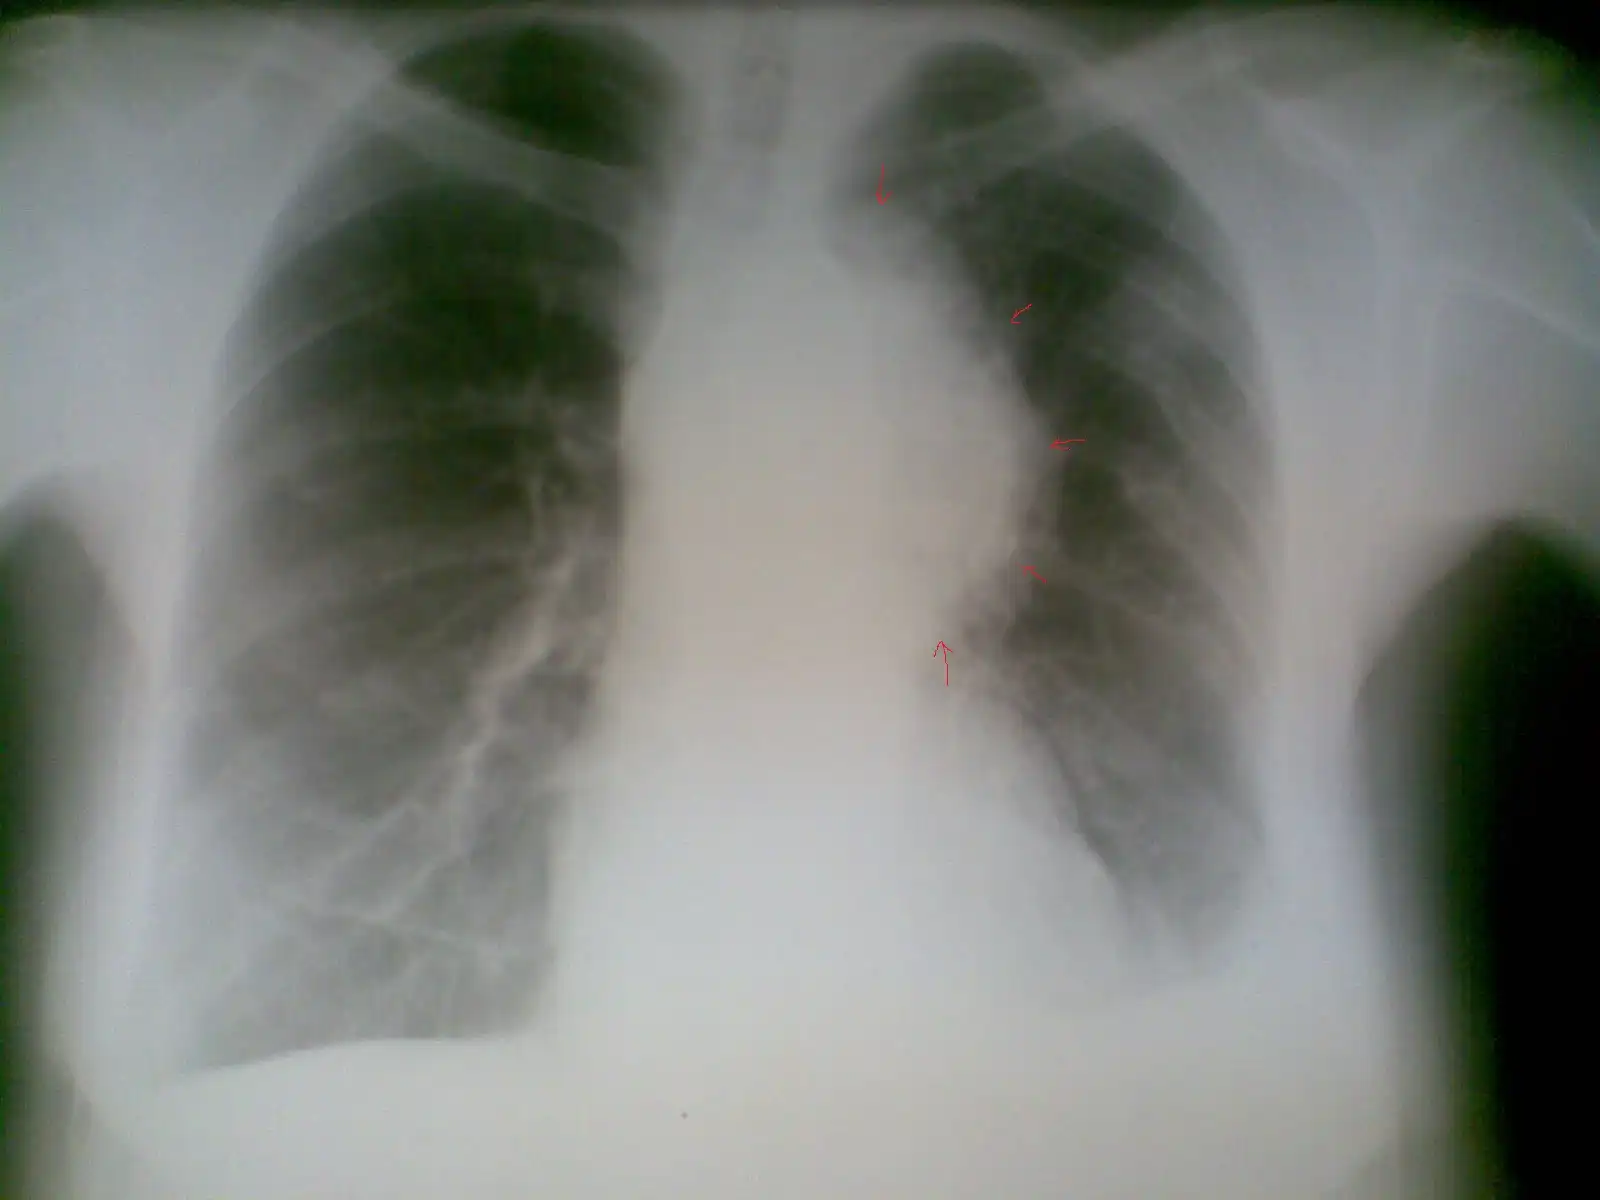

Пациент № 3:

Пациент № 4:

Пациент № 6:

Пациент № 7: